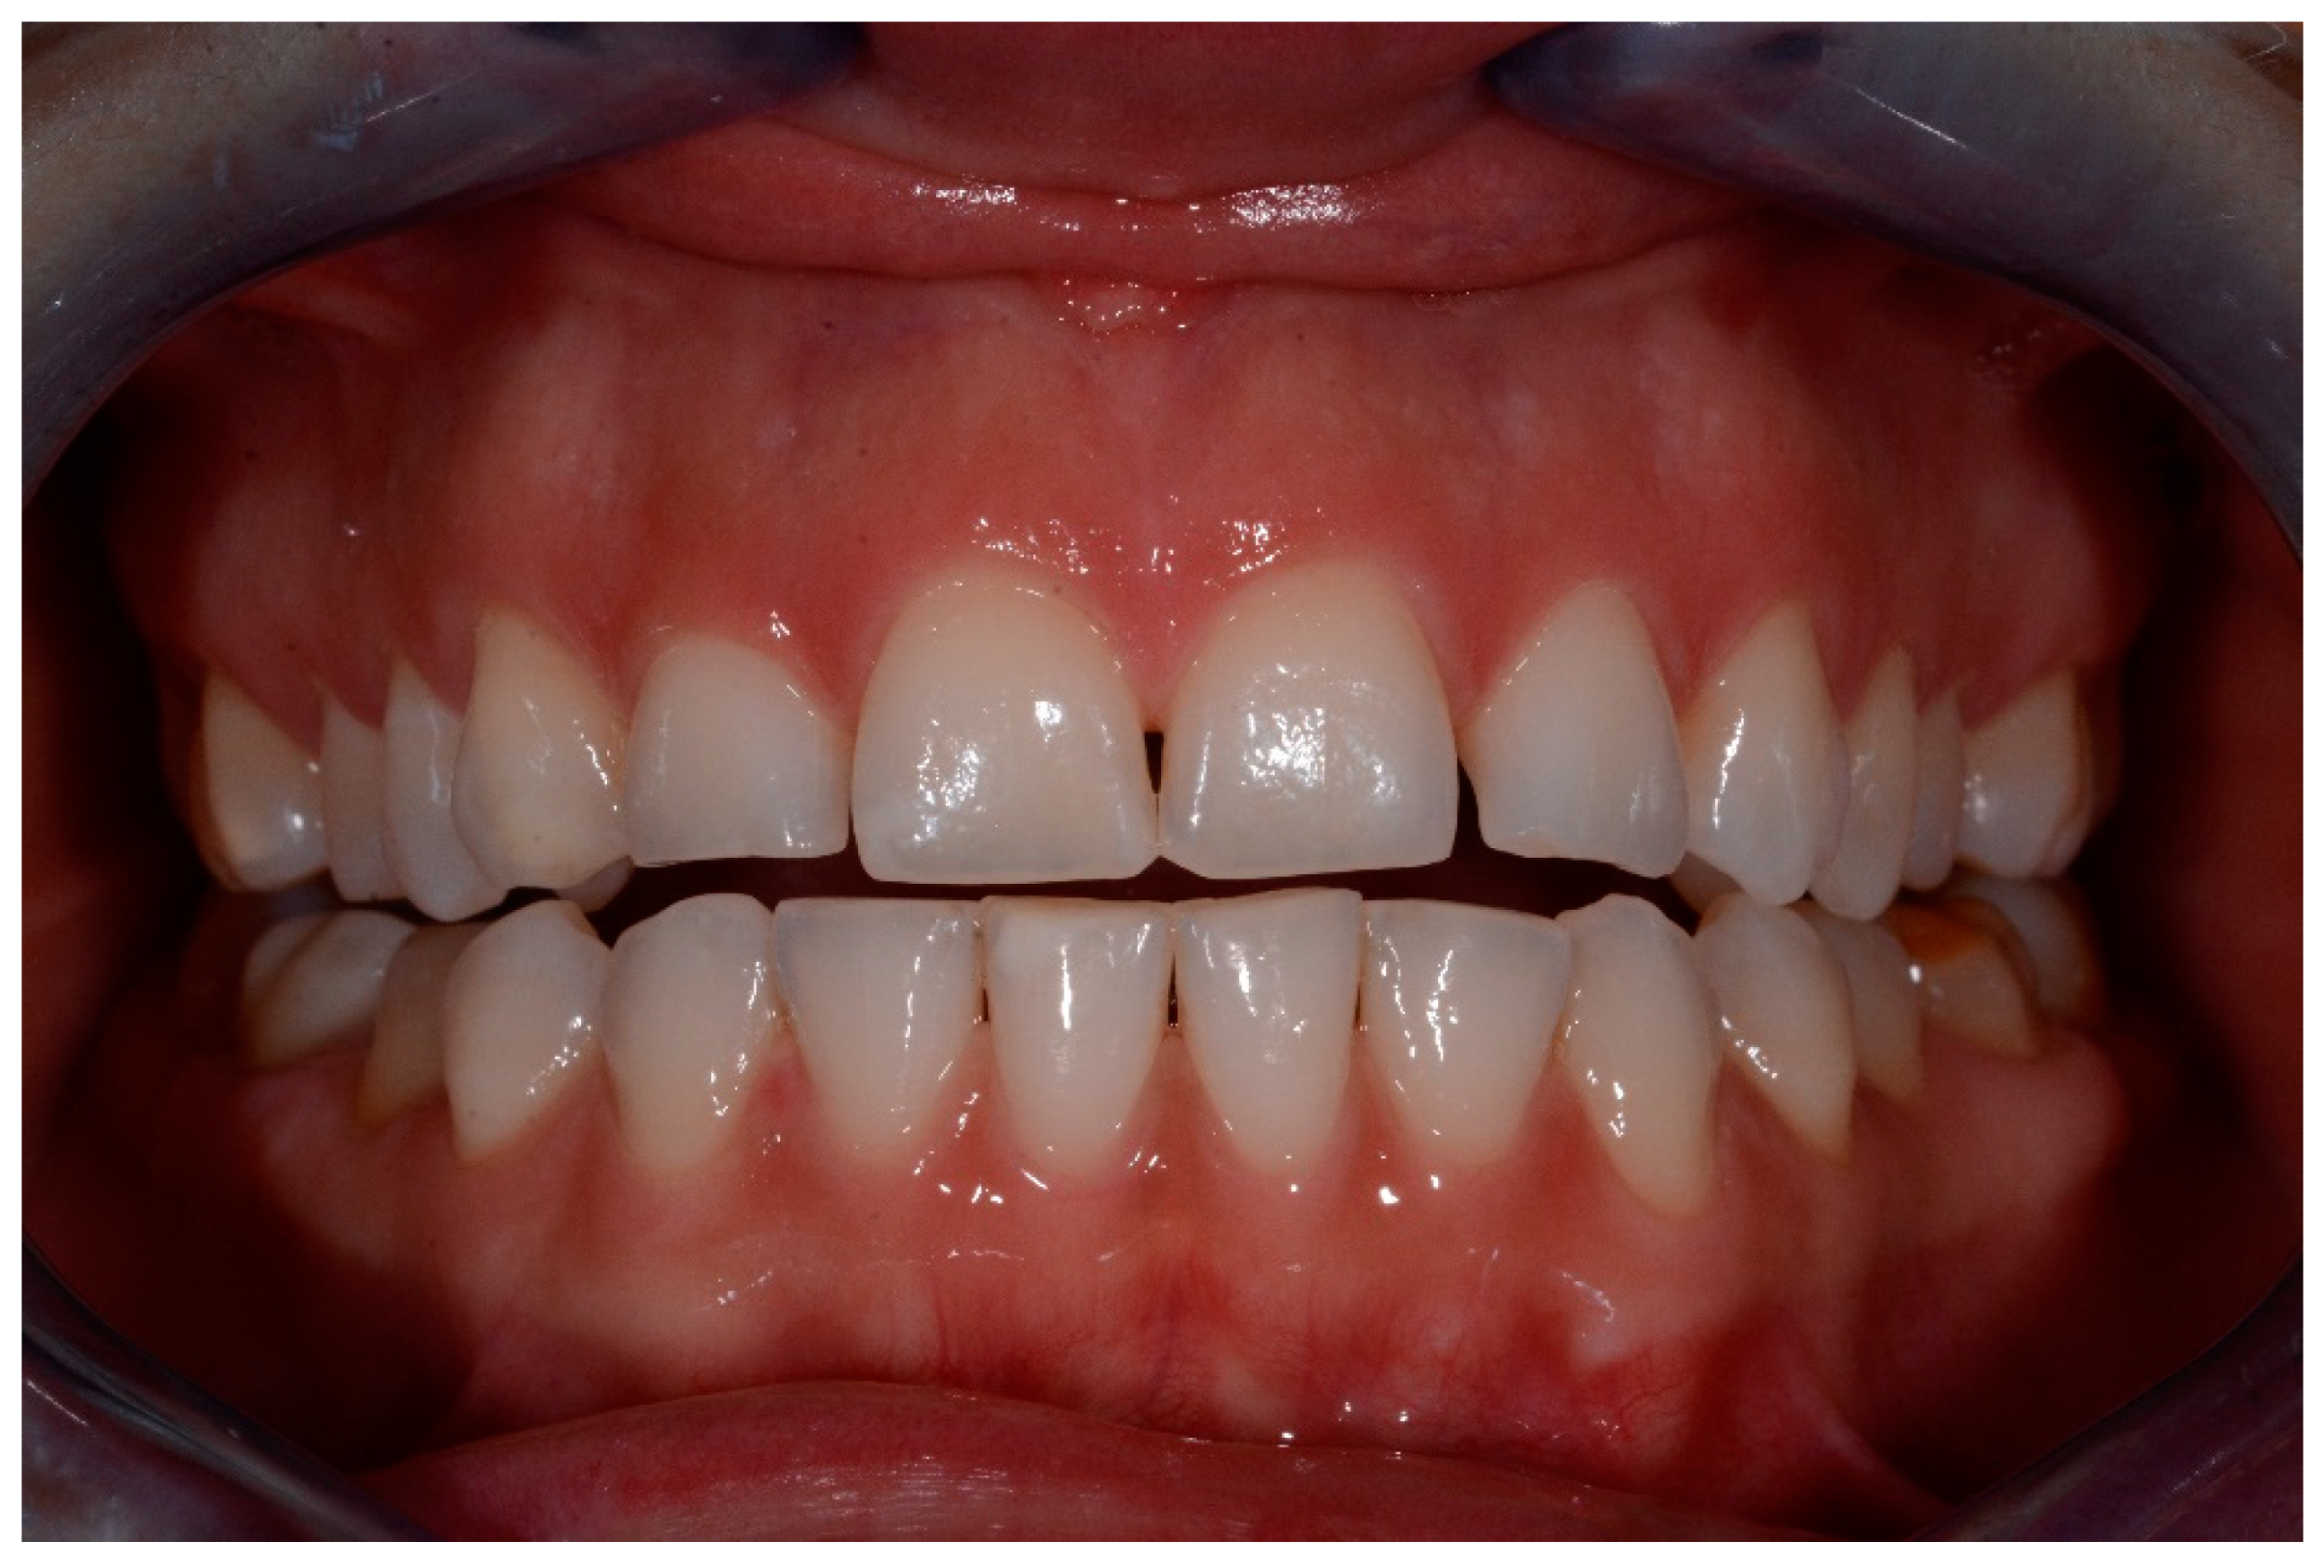

Resin Infiltration in Dental Fluorosis Treatment—1-Year Follow-Up

2. Materials and Methods